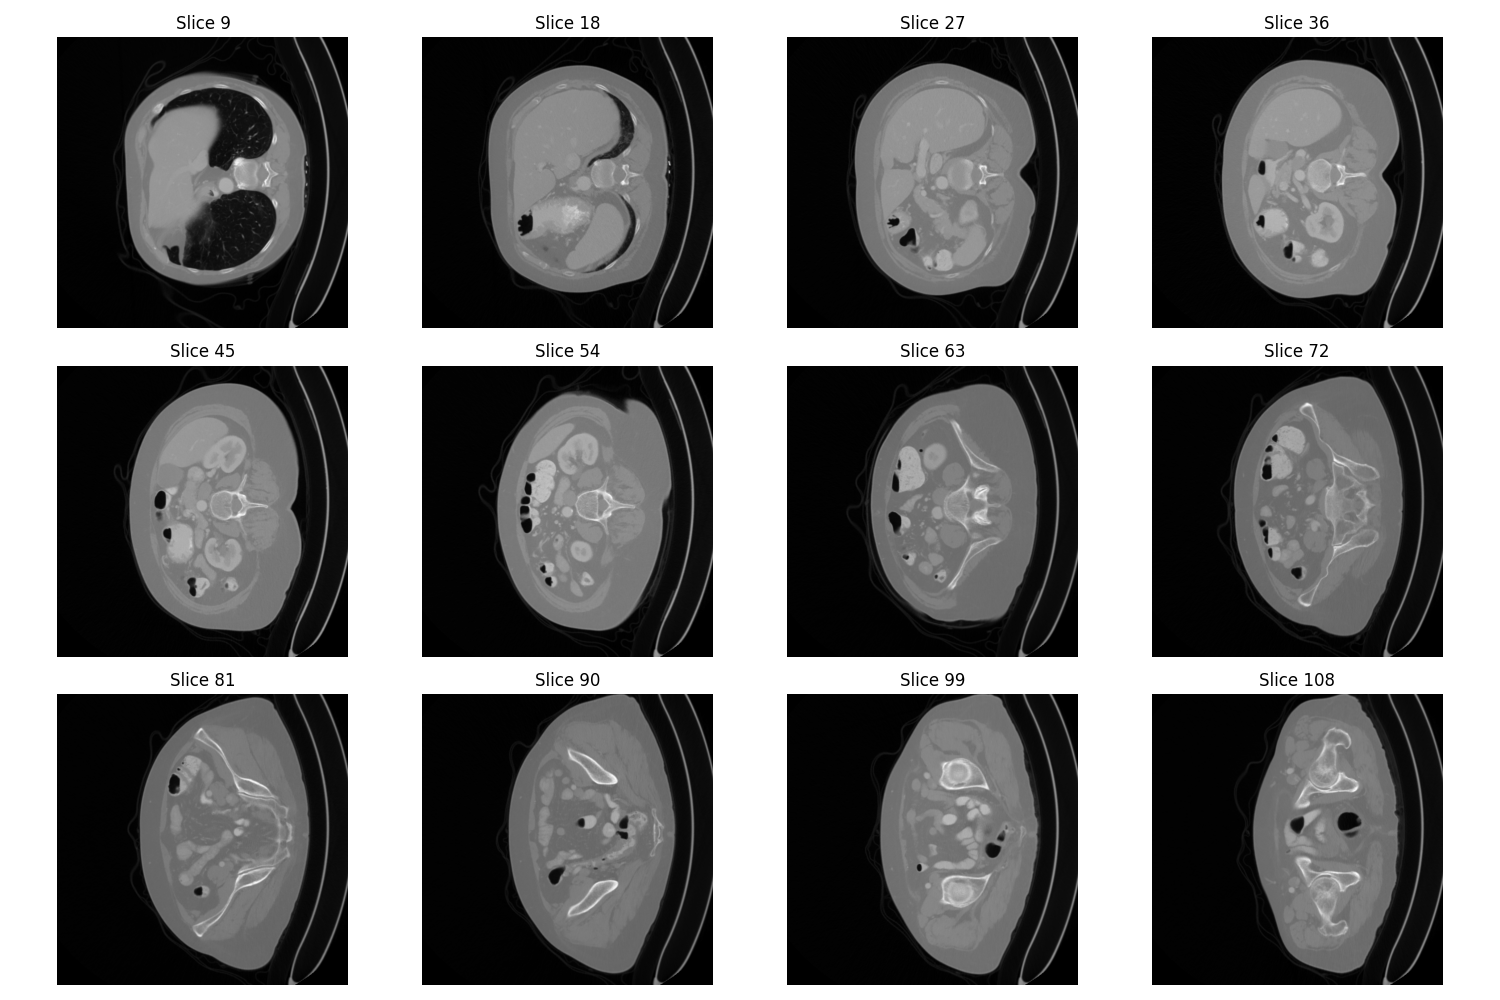

Examples of kidney tumors from different angles

Montage image of a malignant tumor

Montage image of a benign tumor